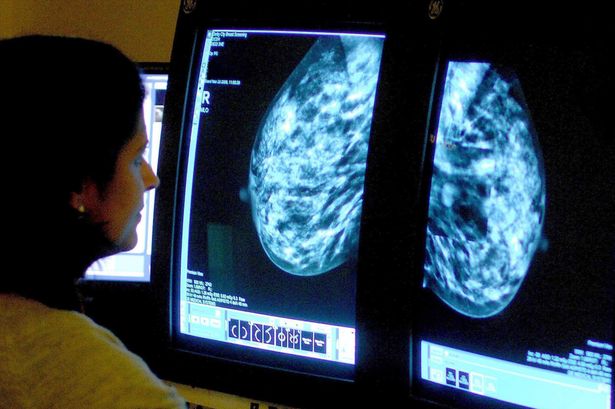

AI in Breast Cancer Screening Could Reveal Heart Disease Risks

Researchers have discovered that artificial intelligence (AI) can uncover signs of heart disease during breast cancer screenings. This innovative approach focuses on detecting calcification in breast arteries, a factor that significantly increases the risk of heart attack, stroke, and premature death. According to a recent study, integrating this technology into existing breast cancer screening programs could identify thousands of women with undiagnosed heart conditions.

Leading the study, Dr. Hari Trivedi from Emory University in Atlanta, highlighted the importance of this research. He noted that heart disease remains the leading cause of death among women globally, yet many are often underdiagnosed and undertreated compared to men. Dr. Trivedi stated, “Mammograms, which women already undergo for breast cancer screening, can also reveal calcium deposits in breast arteries, linked to heart disease. We aimed to determine whether AI could utilize this data to identify women at risk of cardiovascular disease without additional cost or inconvenience.”